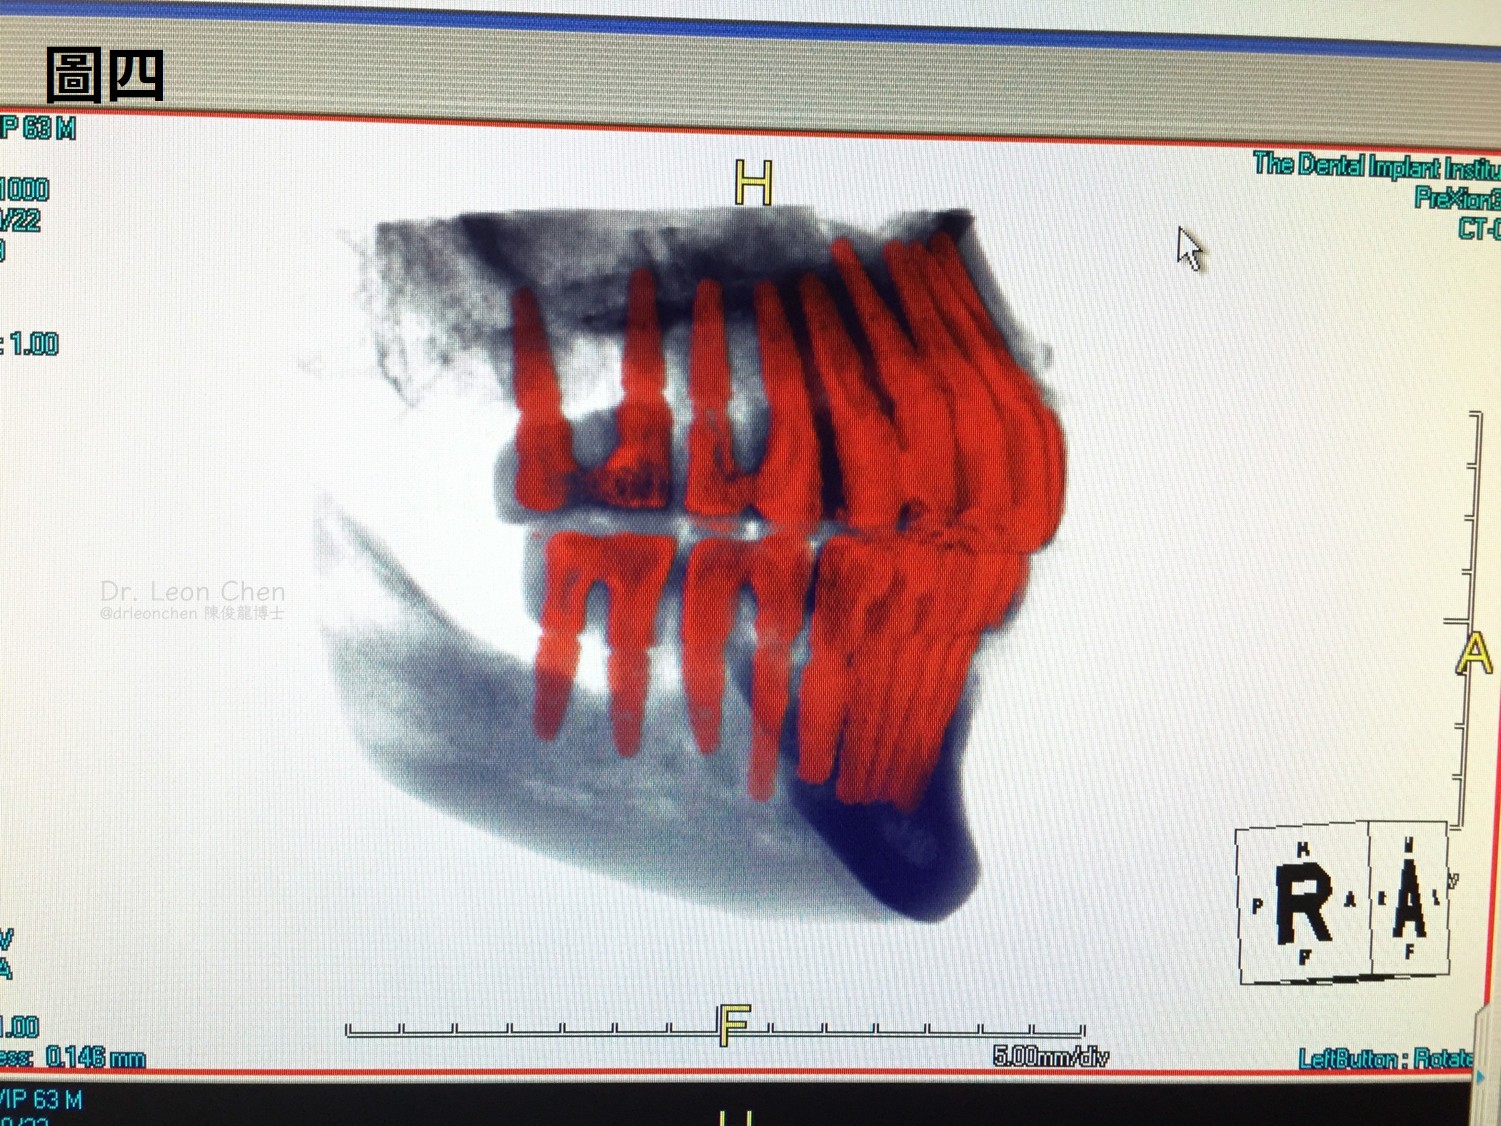

陳博士還分享其他二個全口28顆植牙案例(圖二~圖四),重點都在「角度」。

這些都是17年以上的老病人,持續追蹤、每一顆植牙都穩穩耐用。

雖身為植牙手術醫師,始終堅持 Prosthetic-driven implant planning 的理念,而非僅以骨頭為導向(bone-driven)。

如果單純只看骨頭位置,忽略了假牙的連接方向與咬合設計,最終可能導致修復體無法順利就位,或植體角度過度傾斜,進而增加螺絲(screw)或基台(abutment)斷裂的風險。